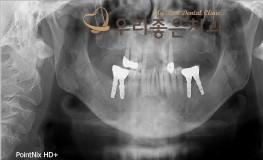

우리좋은치과 치주질환으로 인한 골소실 → 임플란트 보철 치료 (백** 2019.05..

No.346

임플란트

2019-11-25

1545